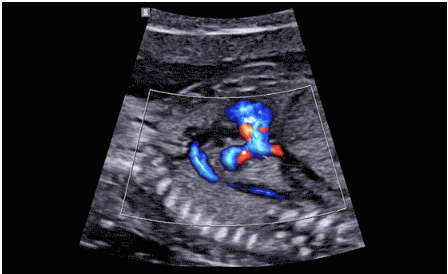

CrystalLive?是三星最新的超聲成像引擎,同時增強了2D圖像處理能力、3D渲染能力和彩色信號處理能力,能夠在復(fù)雜情況下提供出色的圖像性能,具備檢測外周血管、微循環(huán)血流的能力。